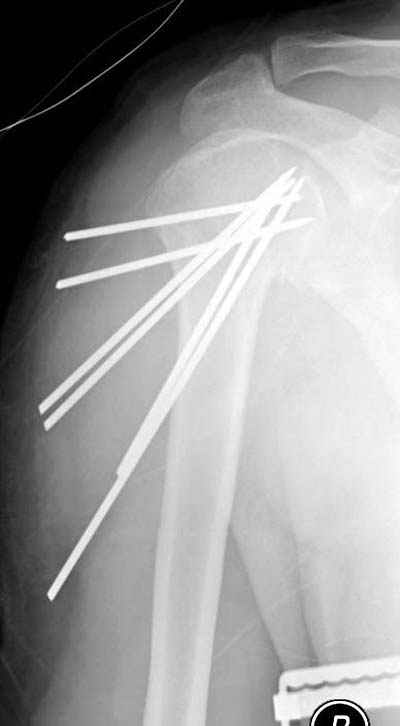

Пока я пользуюсь методикой принятой у нас (методика Сиэтла), также перкутанный спицевой метод, только сцицы 2.8 мм с резбой на конце.

Здесь случай перелома-вывиха плеча, больному 56 лет, после "дважды" закрытой неудачной репозиции, опять же ургентно взяли в операционную, после полного общего обезболивания попытались сделать репозицию, и фиксацию провели спицами.

Больной находился в повязке, примерно напоминяющей косыночную, рекомендованы движения в локтевом суставе и маятниковые движения в плече, спицы удалены в три недели (были случаи миграции)

Больной амбулаторный, предупрежден на случай осложнения АВН головки.